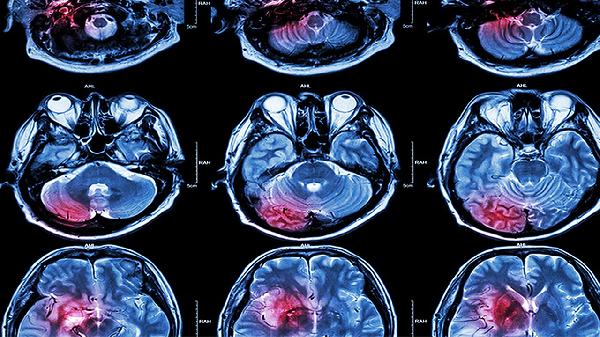

5、颅内病变

脑肿瘤、蛛网膜下腔出血等疾病可引起局部压迫或刺激,导致进行性加重的头痛。可能伴随呕吐、视物模糊等症状。需通过CT或MRI检查确诊,根据病情选择开颅手术或伽马刀治疗。